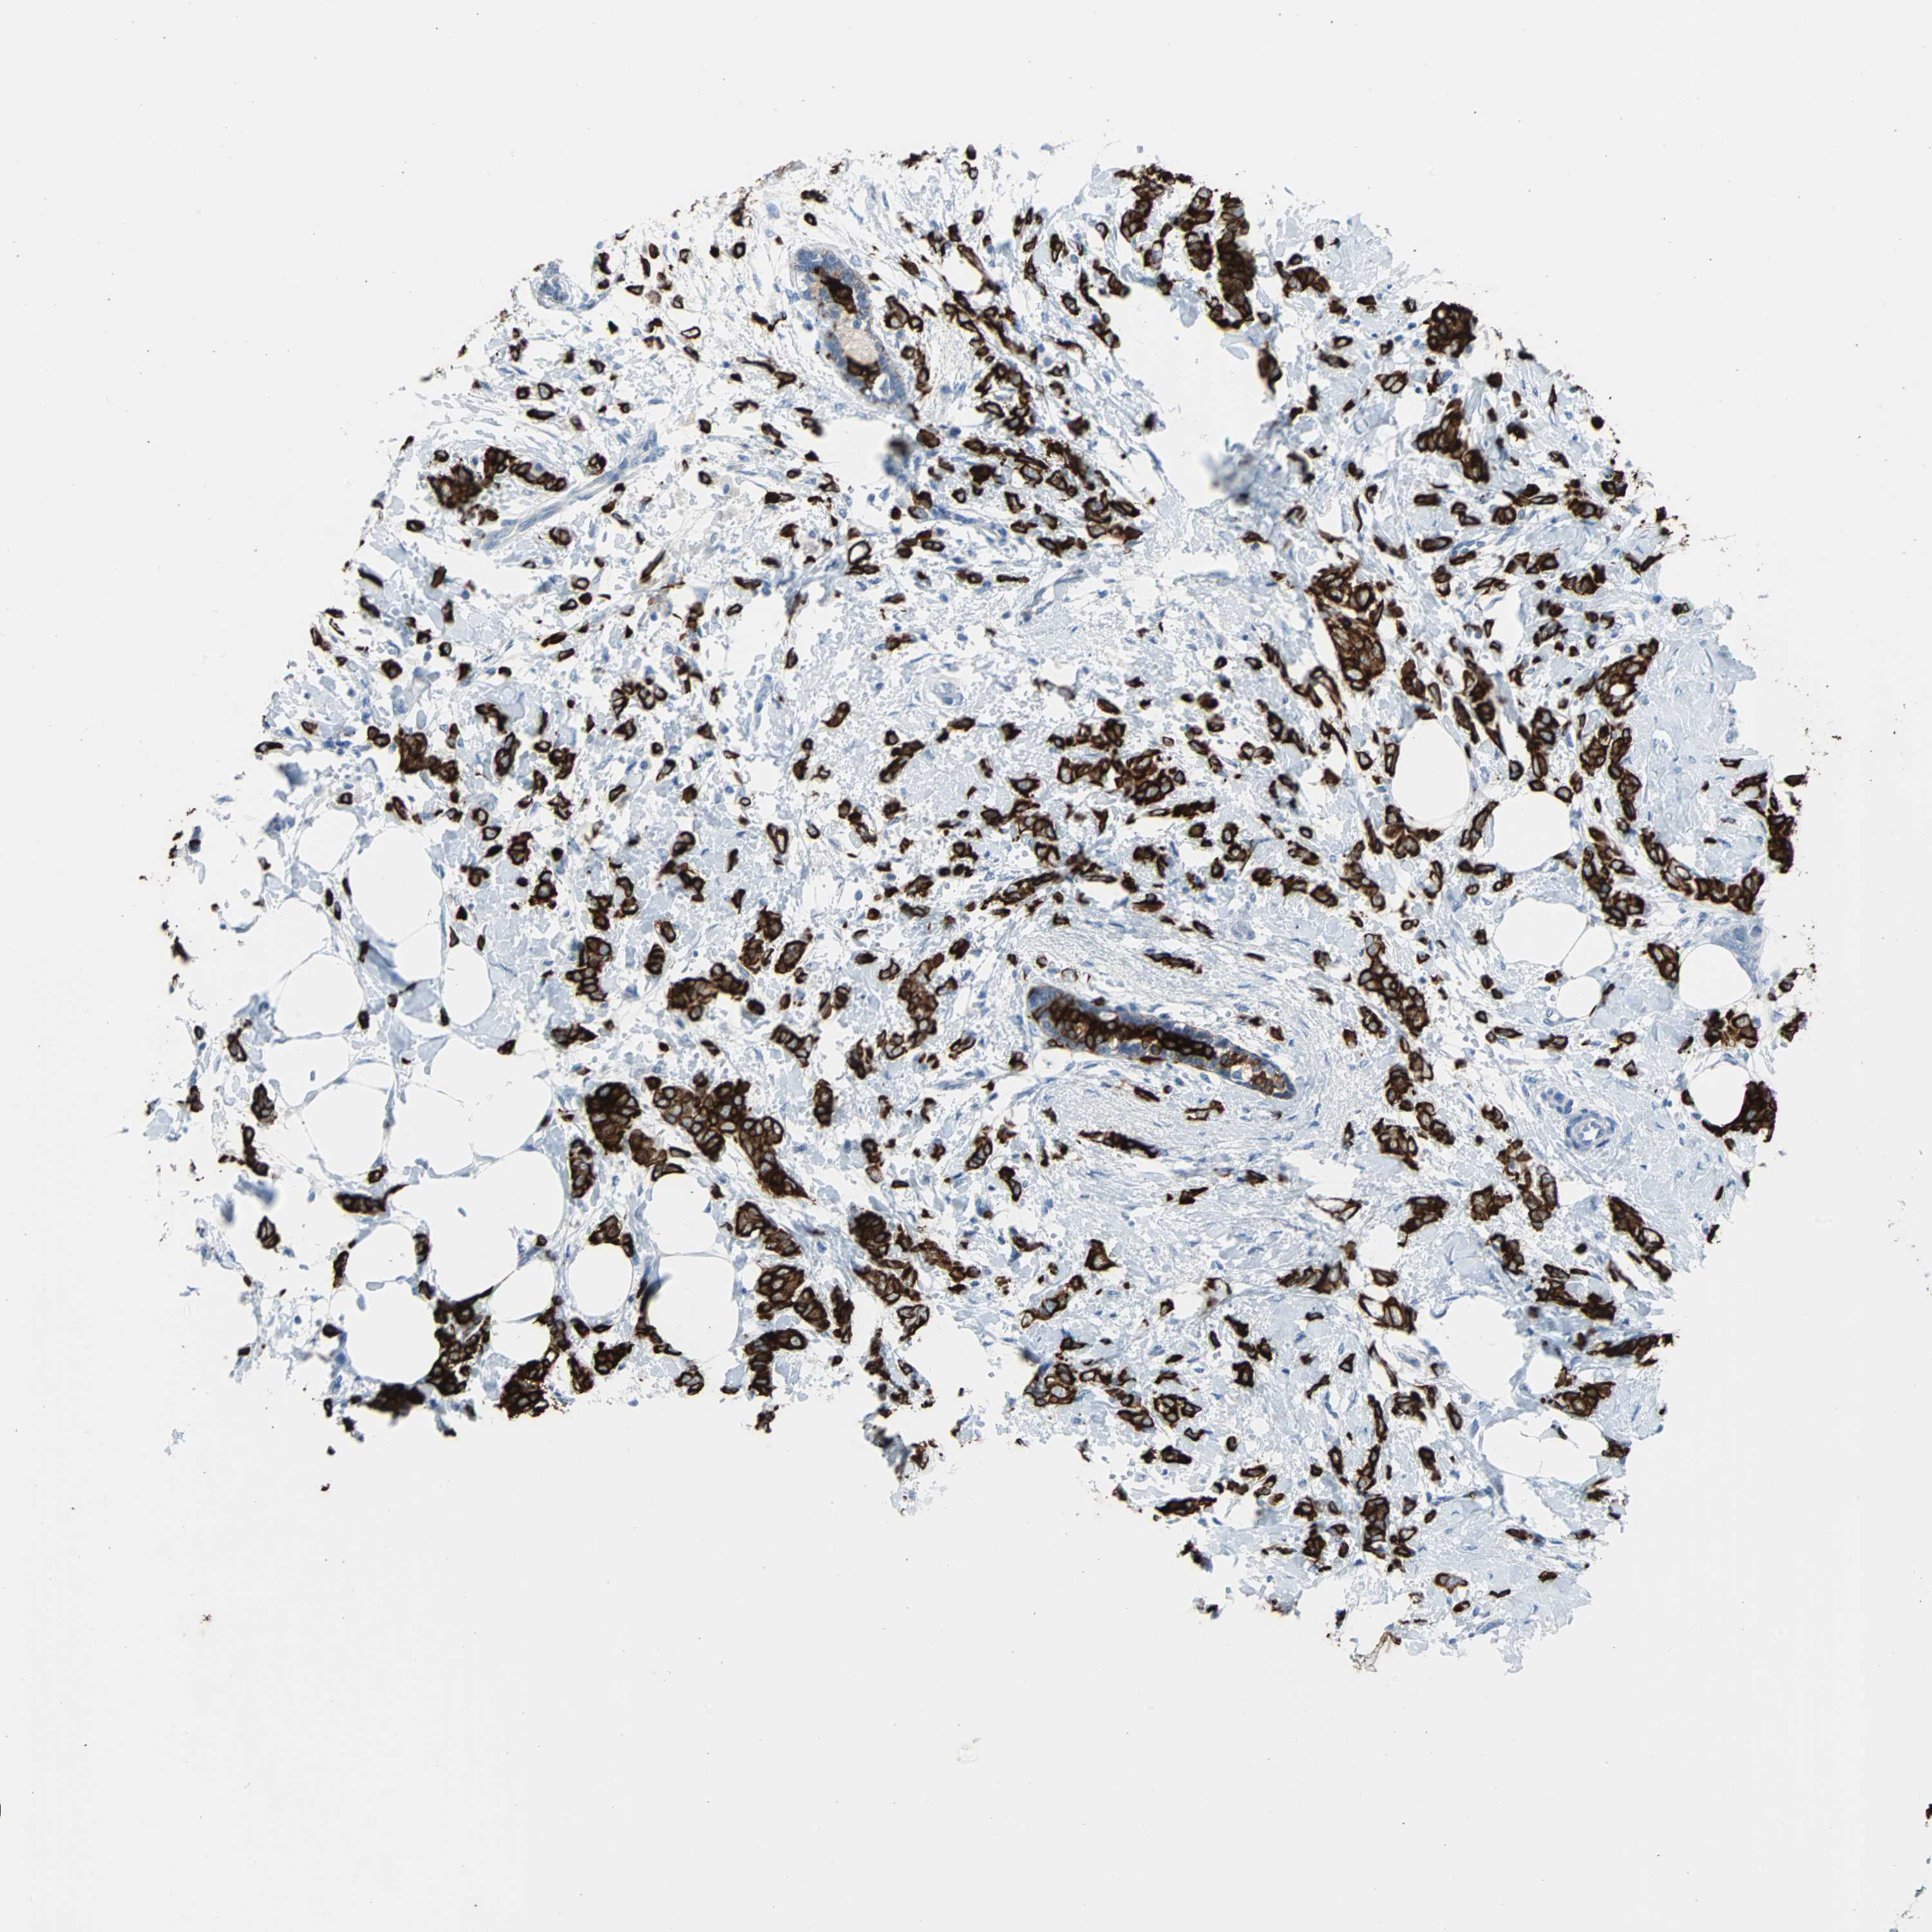

BRCA TCGA BRCA VALIDATION PROTEIN EXPRESSION